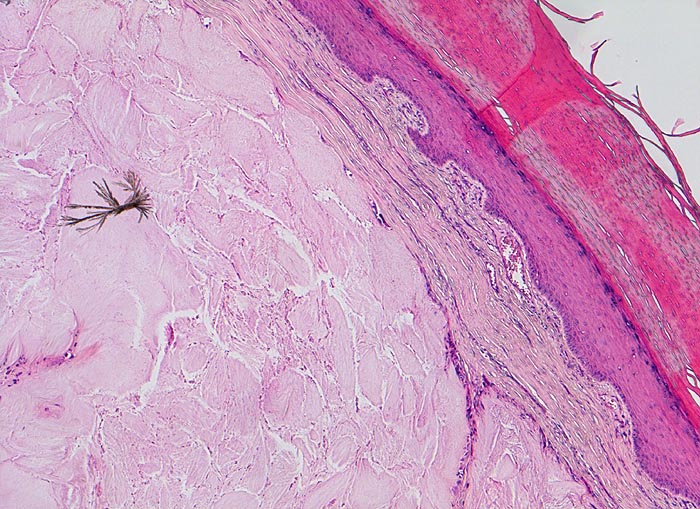

Die nadelförmigen und zu Büscheln angeordneten Natriumuratkristalle zeigen im polarisierten Licht eine starke Doppelbrechung, sind aber wasserlöslich und daher in den üblichen histologischen Schnitten nach Formalinfixierung nicht oder allenfalls noch residuell nachweisbar. Die ebenfalls doppelbrechenden, nicht wasserlöslichen Kalziumpyrophosphatkristalle der Pseudogicht sind kürzer und oft rhomboid geformt.

• Kollagenes Bindegewebe mit Tophus bestehend aus wolkiger eosinophiler Matrix mit herdförmig erkennbaren nadelförmigen Strukturen (Uratkristalle).

• Die Ablagerungen sind umgeben von mehrkernigen Fremdkörperriesenzellen, Makrophagen und wenigen neutrophilen Granulozyten.